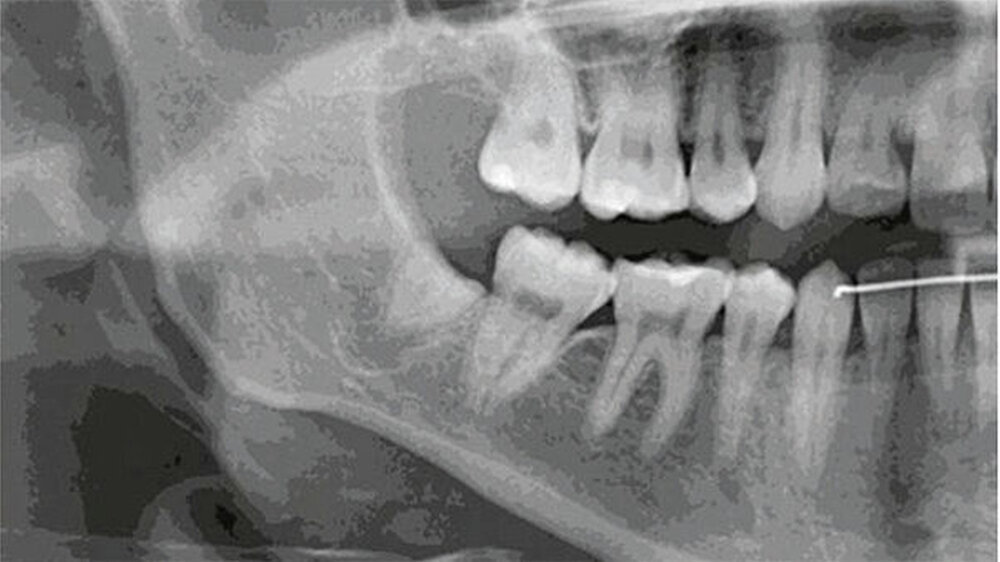

Bei der 27-jährigen, gesunden Patientin, kam es zu rezidivierender Perikoronitis des teilretinierten Zahns 48 (Abb. 1a). Primär wurde eine OPT-Aufnahme zur Operationsplanung erstellt (Abb. 1b). Dabei zeigte sich eine komplette Überlagerung der Zahnwurzel über den C. mandibulae. Zur weiteren Abklärung der Lagebeziehung wurde eine DVT-Aufnahme erstellt (Abb. 1c). Eine linguale Lage des C. mandibulae zur Zahnwurzel konnte festgestellt werden. Eine knöcherne Begrenzung des C. mandibulae zur Zahnwurzel fehlte.